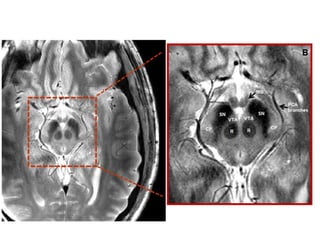

Axial oblique 0.8-mm-thick SSFP MR image

shows the nerve (small arrows) where it

emerges from the interpeduncular cistern

(large arrow), which lies medial to the

cerebellar peduncle (p)

Coronal 0.8-mm-thick SSFP MR image shows

the oculomotor nerve (white arrow) in cross

section between the posterior cerebral artery

(white arrowhead) and the superior cerebellar

artery (black arrowhead), which are distal

branches of the basilar artery (black arrow).

Axial oblique 0.8-mm-thickSSFP MR image shows the nerve (small arrows) where it emerges from the interpeduncular cistern (large arrow), which lies medial to the cerebellar peduncle (p) Coronal 0.8-mm-thick SSFP MR image shows the oculomotor nerve (white arrow) in cross section between the posterior cerebral artery (white arrowhead) and the superior cerebellar artery (black arrowhead), which are distal branches of the basilar artery (black arrow).